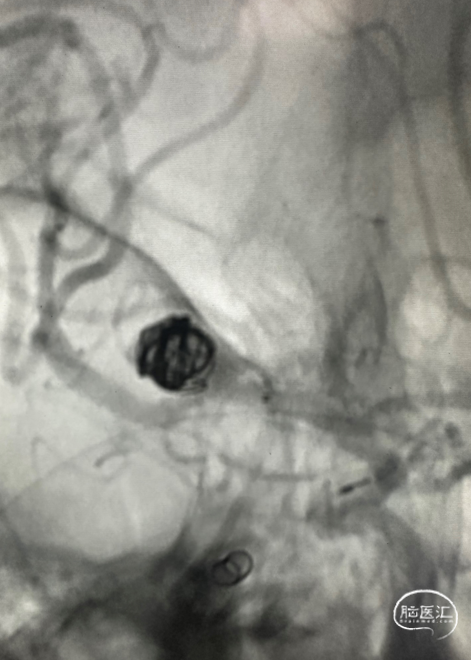

手术过程

微导管到位。

在瘤体置入首枚7*30cm弹簧圈成篮时,有少部分圈突至下干支狭窄处。

故半释放一枚LEO Baby 2.5*18mm支架,在瘤颈处进行推挤呈“灯笼”状;

再依次置入6*20cm、4*10cm、2*6cm三枚弹簧圈,全释放支架,完成治疗。